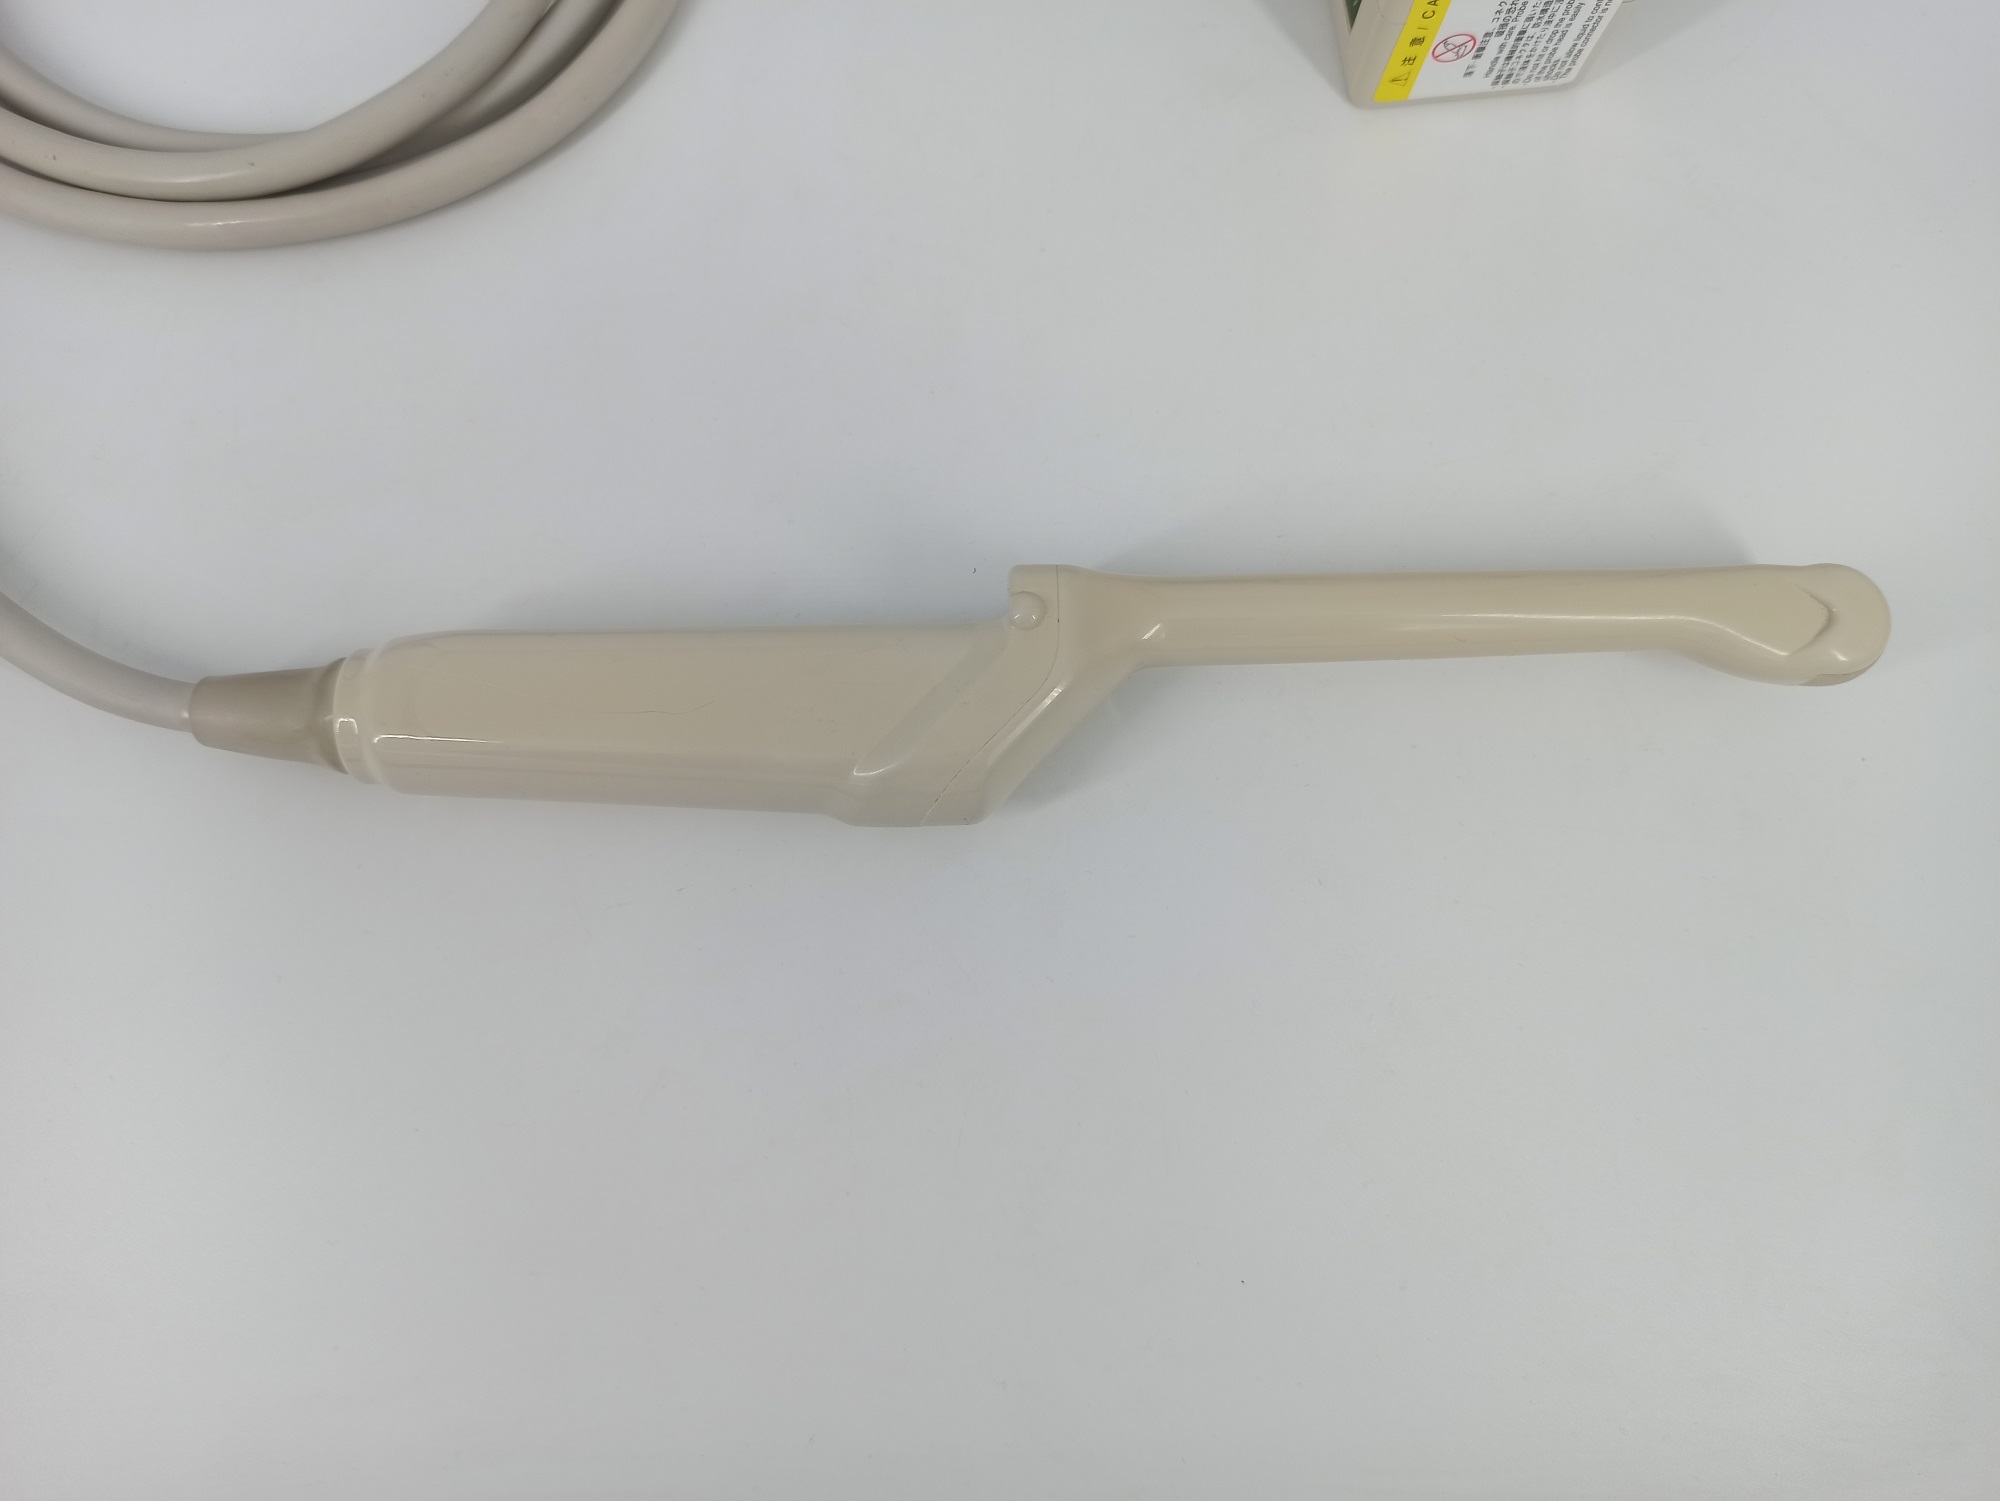

Hitachi EUP-V53W Ref Endocavity Vaginal – HI VISION

Hitachi Endocavity EUP-V53W Transvaginal

Hitachi EUP-V53W Endocavity Vaginal – HI VISION

Hitachi EUP-V53W Endocavity Vaginal – HI VISION for Endovaginal

Compatible with Hitachi Hi Vision systems